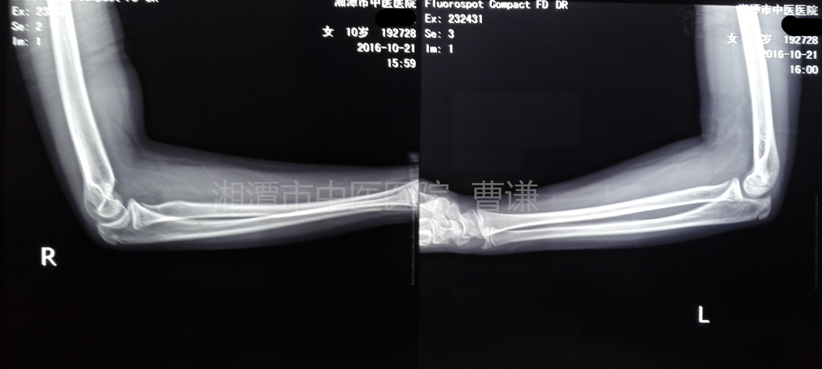

治療一年后隨訪拍片

隨訪一年,功能恢復(fù)良好,外觀無肘內(nèi)翻畸形。